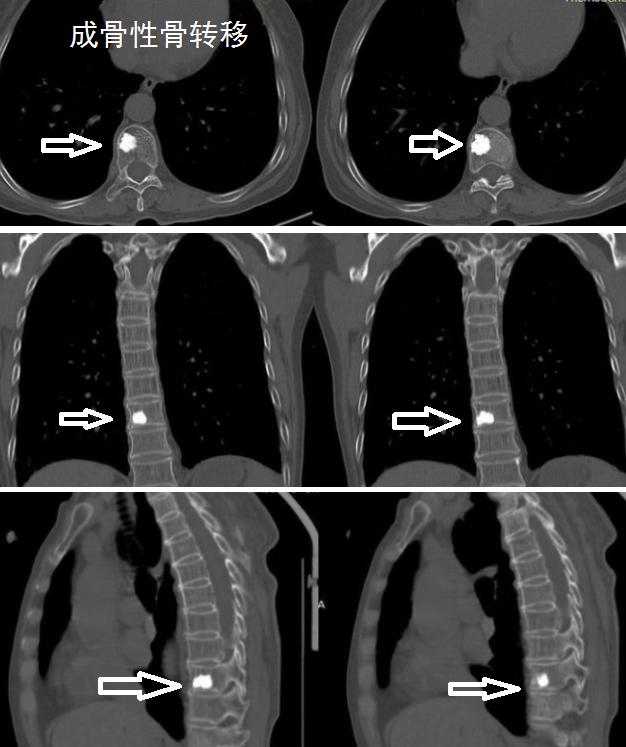

Pain caused by bone metastasis typically occurs in fixed locations, is severe, persistent, and unbearable

Different sites of metastasis present with corresponding characteristics. Rib metastases often cause chest pain, manifesting as localized pain in the chest wall with specific tender points. Spinal metastases lead to pain in the midline of the back or at the site of the lesion, along with symptoms of spinal cord compression. Metastases in the limbs or trunk result in localized pain and radiating pain at the metastatic sites.